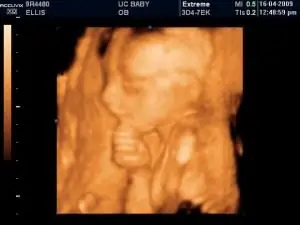

Размышляющий Фото этого маленького ребенка получили

выложили на сайте BabyGaga в рамках конкурса на лучшее фото УЗИ. Эта недоношенная милашка напоминает мне бронзовую статую «Мыслителя». Поскольку этот ребенок держится за подбородок, а не кладет на него голову, я предполагаю, что он глубоко задумался, и называю его/ее «задумчивым». Возможно, ему интересно, когда же он войдет в землю.